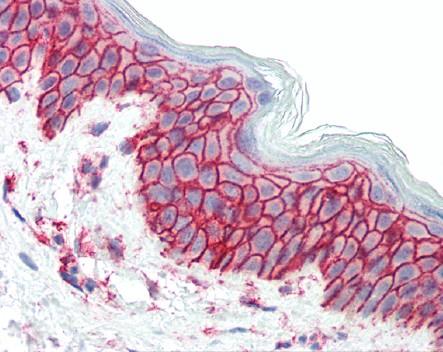

免疫组织化学是利用抗原抗体的特异性结合的原理,通过化学反应使标记抗体的显色剂 (荧光素、酶、金属离子、同位素) 显色来确定组织细胞内抗原(多肽和蛋白质),对其进行定位、定性及定量的研究。免疫组织化学染色技术不仅有较高的敏感性和特异性,其特点是将形态学改变与功能、代谢变化结合起来,直接在组织切片,细胞涂片或培养细胞爬片上定位一些蛋白质和多肽类物质的存在,并可精确到亚细胞结构水平,结合电子计算机图像分析系统或激光扫描共聚集显微术等技术,对被检物质进行定量分析。

免疫组织化学染色方法 IHC染色方法有很多种,按部标记物的性质可分为荧光法(荧光素标记),酶法(辣根过氧化物酶,碱性磷酸酶),免疫金银及铁标记技术等;按染色步骤可分为直接法(又称一步法)和间接法(二步,三步或多步法);按结合方式可分为抗原-抗体结合,如PAP法和标记的葡聚糖聚合物(labeled dextran polymer,LDP)法,以及亲和连接,如ABC法、标记的链亲和素-生物素(labeled streptoavidin-biotin ,LSAB)法等,其中LSAB是最常用的使用方法。